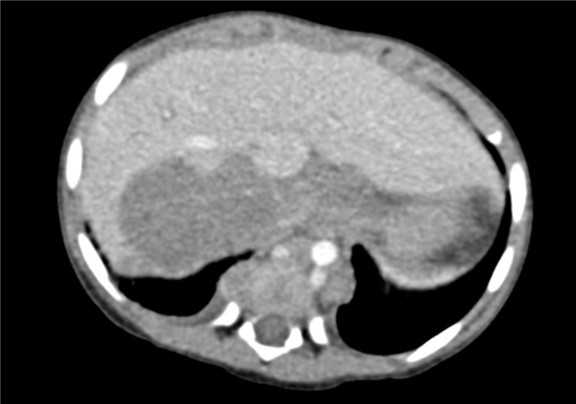

下腹部增强CT示:右肾上腺区占位并周围侵犯,腹腔、腹膜后多发淋巴结肿大,考虑恶性肿瘤,神经母细胞瘤?胆囊炎可能性大。

术前CT检查:

静脉期